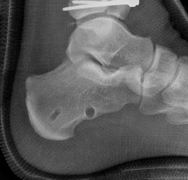

Image

The CT scan allows the surgeon to map the fracture lines, identify the primary articular fragments (Chaput, Volkmann, medial malleolus), and quantify the degree of central die-punch impaction. In an AO/OTA 43C3.3 fracture, where no articular fragment is in continuity with the diaphysis, the surgeon must plan the sequence of reduction. Typically, the fibula is addressed first to restore lateral column length and rotation, provided the fibular fracture is not located at the level of the syndesmosis where fixation might interfere with the lateral surgical approach to the tibia.